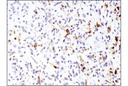

EGF Receptor vIII (D6T2Q) XP Rabbit mAb